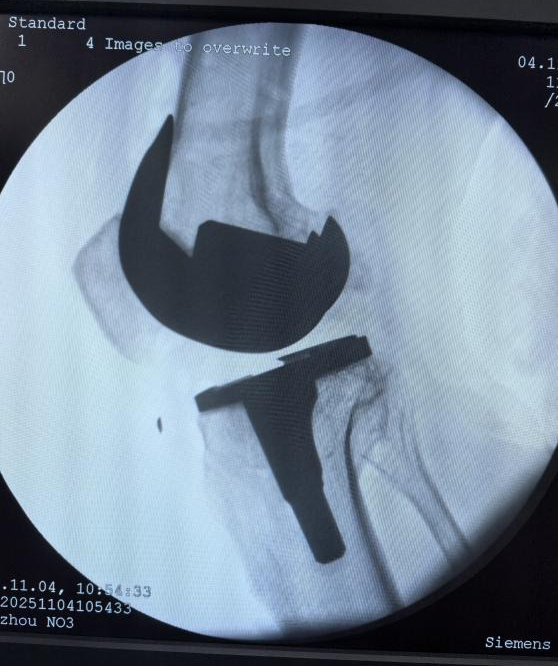

11月4日上午,我院骨科团队成功完成首例骨科机器人辅助全膝关节置换手术,标志着我院骨科诊疗技术正式迈入智能化、精准化、微创化的新阶段,推动了郴州地区骨科手术由传统手术向智能化发展迈出了一大步。

骨科主任胡伟文教授介绍,与传统手术相比,机器人辅助手术如同为医生装上了“透视眼”和“稳定手”。本次手术中,胡伟文主任团队借助先进的骨科手术机器人系统,术中在患者股骨和胫骨上安装追踪阵列及检查点针来精准导航,并采集患者的术前力线和膝关节运动范围等资料,通过机器人的精准计算规划出关节假体的尺寸、安装位置和关节间隙等,医生确认后由机器人的机械臂按照预设的最优方案稳定运行,精准抵达预定位置,有效规避了重要的神经和血管,将手术创伤降至最低。整个手术流程流畅,术中出血少,大大提升了手术质量和安全性。

机器人辅助手术在精准度方面实现了质的飞跃,其截骨精度可达0.1毫米以内,角度误差控制在0.1°以内,综合定位误差仅为0.87毫米,使假体与骨骼贴合度更好,力线恢复更准确,有望延长假体使用寿命。此外,系统基于术中精准的数据采集,智能生成手术方案并允许医生调整个性化手术方案,真正实现“一人一策”,使手术方案与患者个人解剖结构高度匹配。

据了解,该手术由骨科主任胡伟文教授团队联合我院麻醉科手术室等相关科室协作完成。患者为一名膝关节严重退变的老人,术后次日即可下床活动,目前恢复良好。手术的成功开展,不仅体现了医院骨科在微创和智能化技术领域的深厚积累,也展现了多学科协作(MDT)模式下医疗技术的综合创新实力。